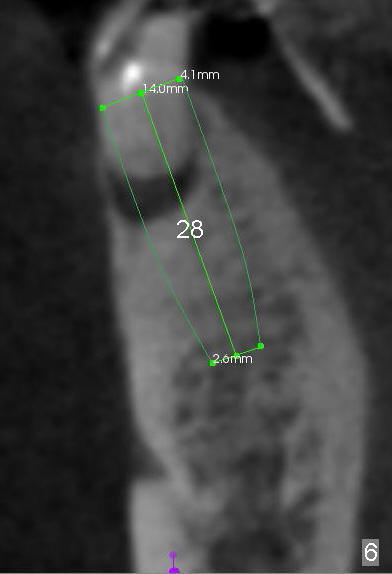

A 85-year-old man has poor dentition (Fig.9). Multiple implants are to be placed at one or two stages (#26-30). If primary stability is obtained for individual implants, they are splinted and immediate provisional is fabricated.

Fig.1-3 are CBCT sagittal sections of the lower right quadrant, whereas Fig.4-8 are coronal sections. The lower left quadrant has been restored.

The sockets of #27,28 will be treated with 2% Xylocaine/1.:50,000 Epinephrine as control group of the antibiotic study.